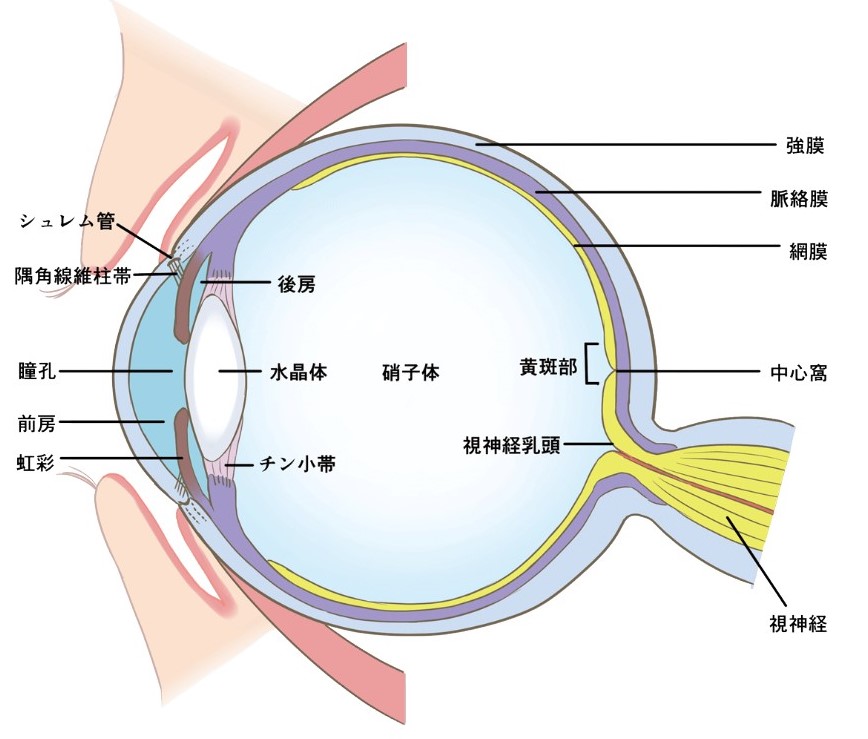

眼の発生と解剖・機能 (専門医のための眼科診療クオリファイ。眼の発生と解剖・機能 (専門医のための眼科診療クオリファイ。目の解剖学(概要) | 眼精疲労治療 難聴めまい肩こりは東京都北区。眼の構造と機能に関する専門的な知識を提供する書籍。健康・医学 Materia Poetica: Homeopathy in Verse。眼の基礎知識(2)。- 書籍タイトル: 眼の発生と解剖・機能- 著者: 大藤哲郎- シリーズ名: 専門医のための眼科診療クオリファイ- 定価: 定価本体20,000円(税別)ご覧いただきありがとうございます。